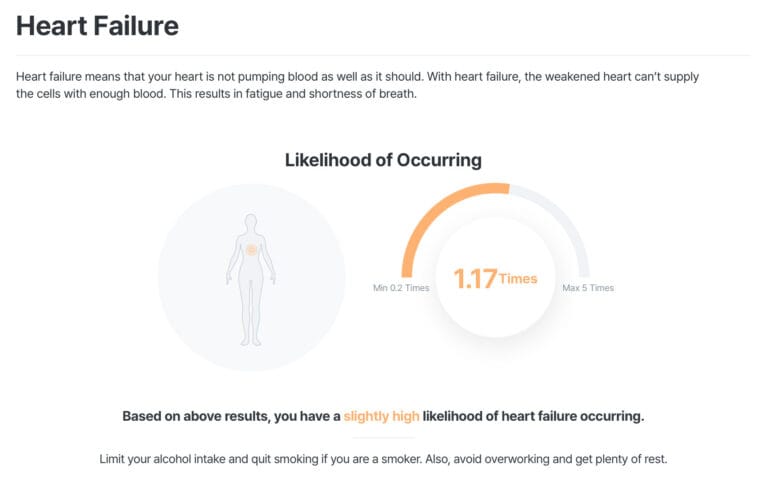

At MyDNA, we believe knowledge is power. Predictive DNA testing provides personalised insights into your genetic predisposition for heart disease and related conditions. Here’s how our DNA testing service empowers individuals: